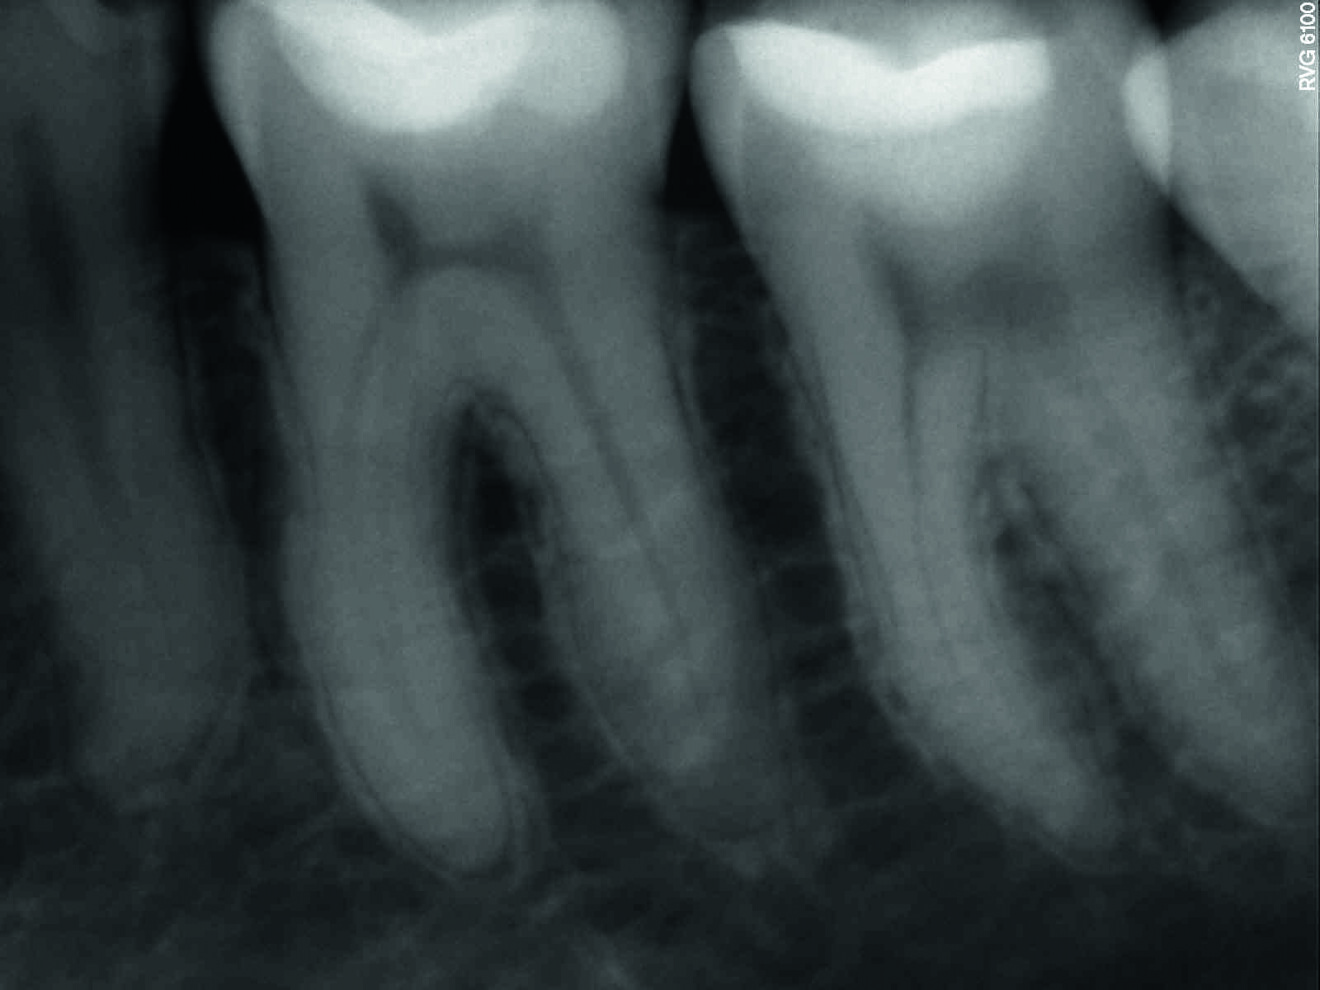

Les figures 9 et 10 montrent des images de radiographie numérique à un an et à douze ans de rappel après la reconstitution de la dent en technique Bio-Bulk Fill avec la Biodentine et le composite. La dent est vitale et aucune image périapicale n’est visible. Aucune rétraction pulpaire n’est observée, ce qui confirme la biocompatibilité de Biodentine.

Fig. 9 : Radio à un an de suivi.

Fig. 10 : Radio à 12 ans de suivi.